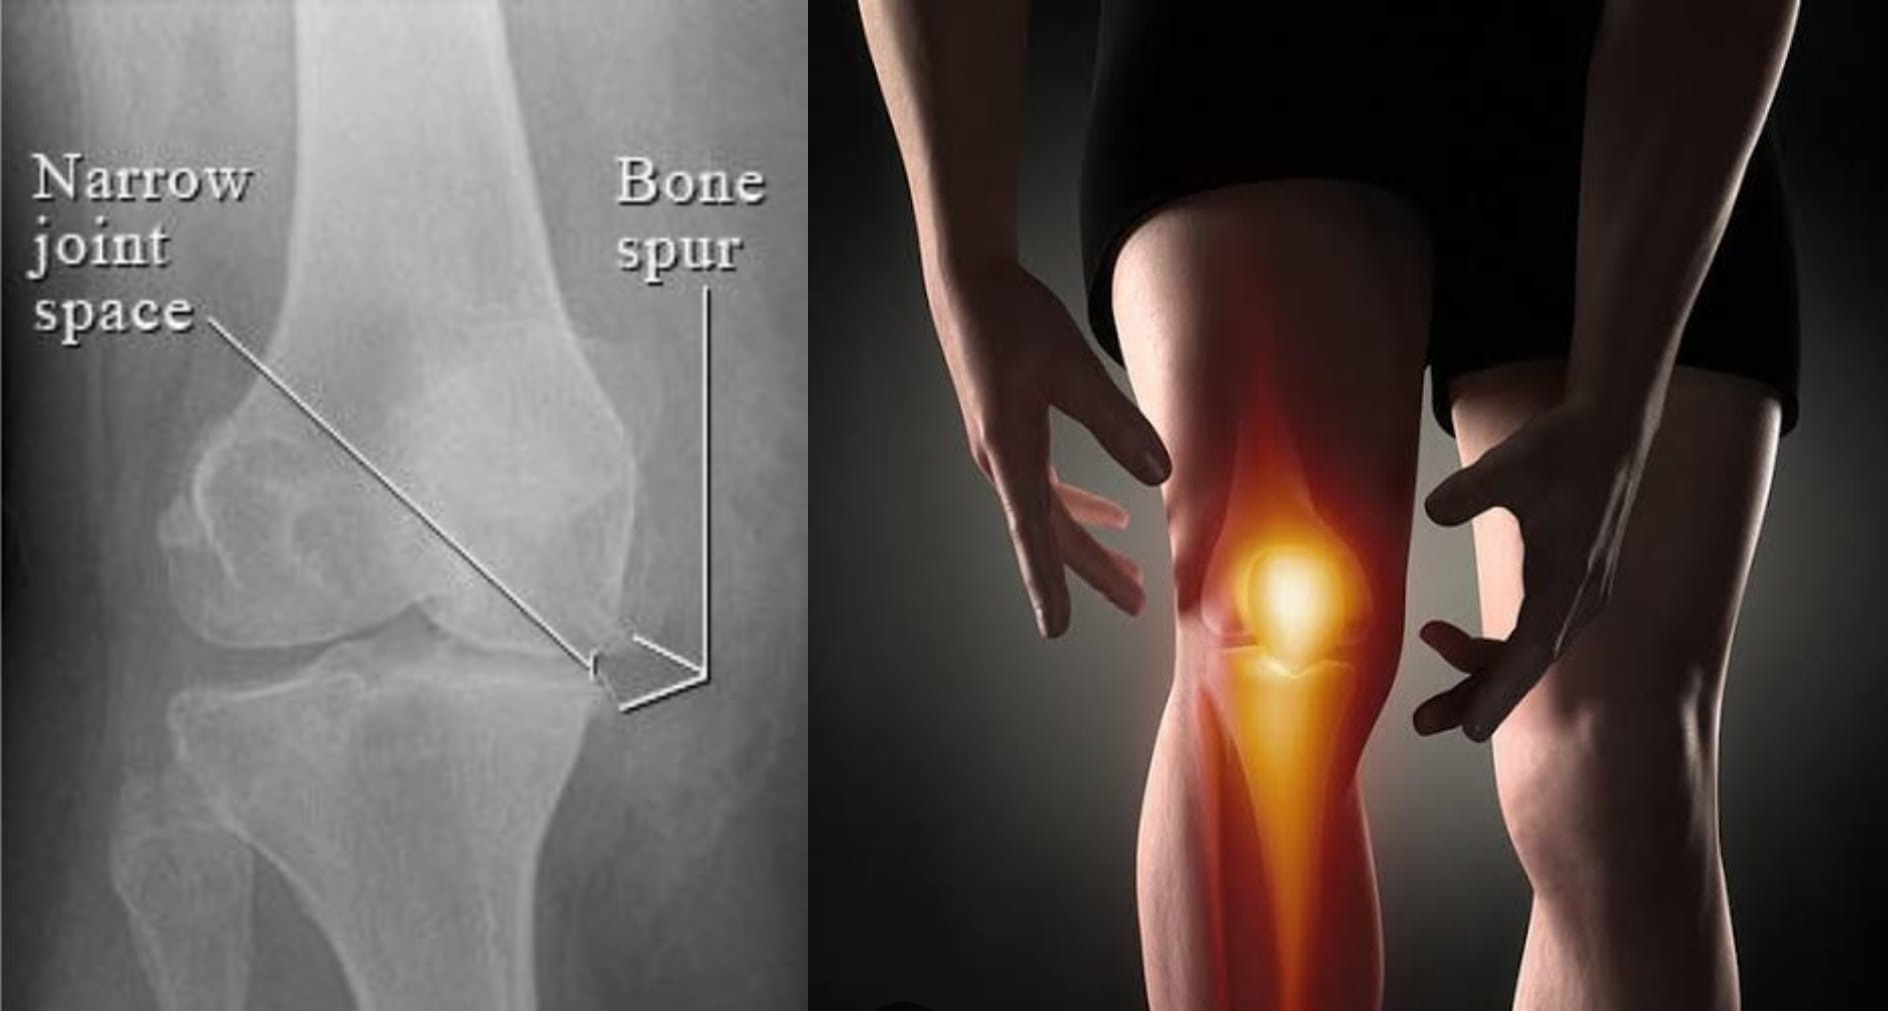

Knee pain treatment without surgery:

Various knee arthritis problems have a lasting solution in homeopathy in form of hollistic medication, supplements and pain relieving balms.